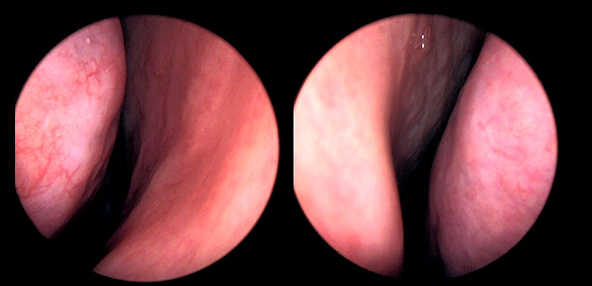

본 사진은 의료기관에서 진료를 본 환자이고, 전후 사진 인물이 동일인이며,동일조건에서 촬영이 되었습니다.